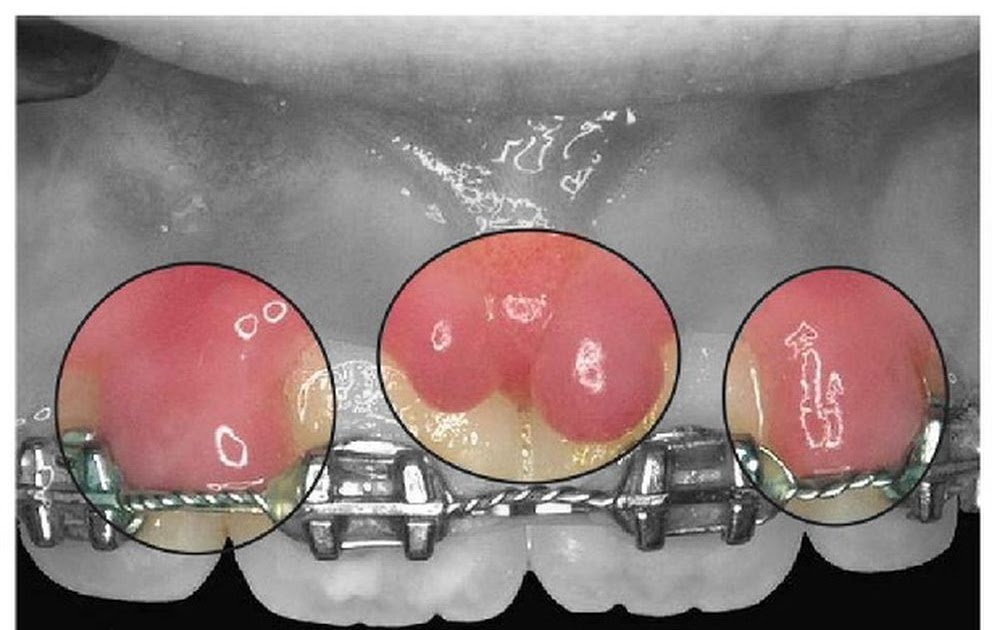

Why Are My Gums Swelling Over My Braces . here are some tips to help relieve your swollen gums. Learn what causes swollen, puffy gums and how to maintain good oral health with braces. If your gums swell after your braces are installed or adjusted, the symptoms may disappear after a few days. And if you thought braces were innocent, think again. While it is relatively common, it is also easy to fix. how to get rid of swollen gums with braces. when you have swollen gums around braces, you’ll tend to notice gingival tissues that are puffiest where they’re close to your appliances. gingivitis, an early stage of gum disease, can be a major culprit behind gum swelling. help relieve swollen gums with braces with these tips from parodontax. Ensure the water isn’t too warm, or you could further irritate your gums. Rinse with warm salt water to soothe puffy gums from braces. swelling and pain in your gums is not a pleasant thing to endure.